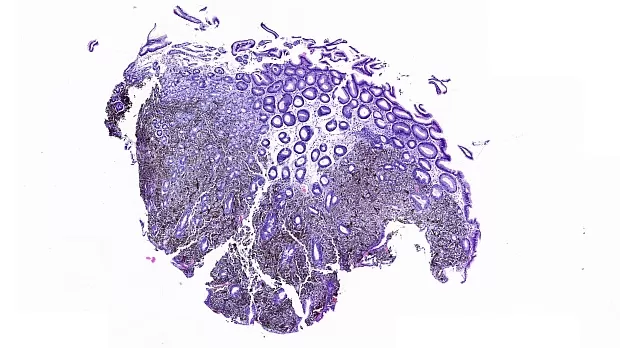

В луковице ДПК и постбульбарного отдела ДПК прослеживаются множественные пигментированные эпителиальные образования темно-черной-синей окраски, размерами до 5 мм, биопсия-гистология №1.

Заключение гистологии: В слизистой желудка рост пигментной эпителиоилноклеточной меланомы.